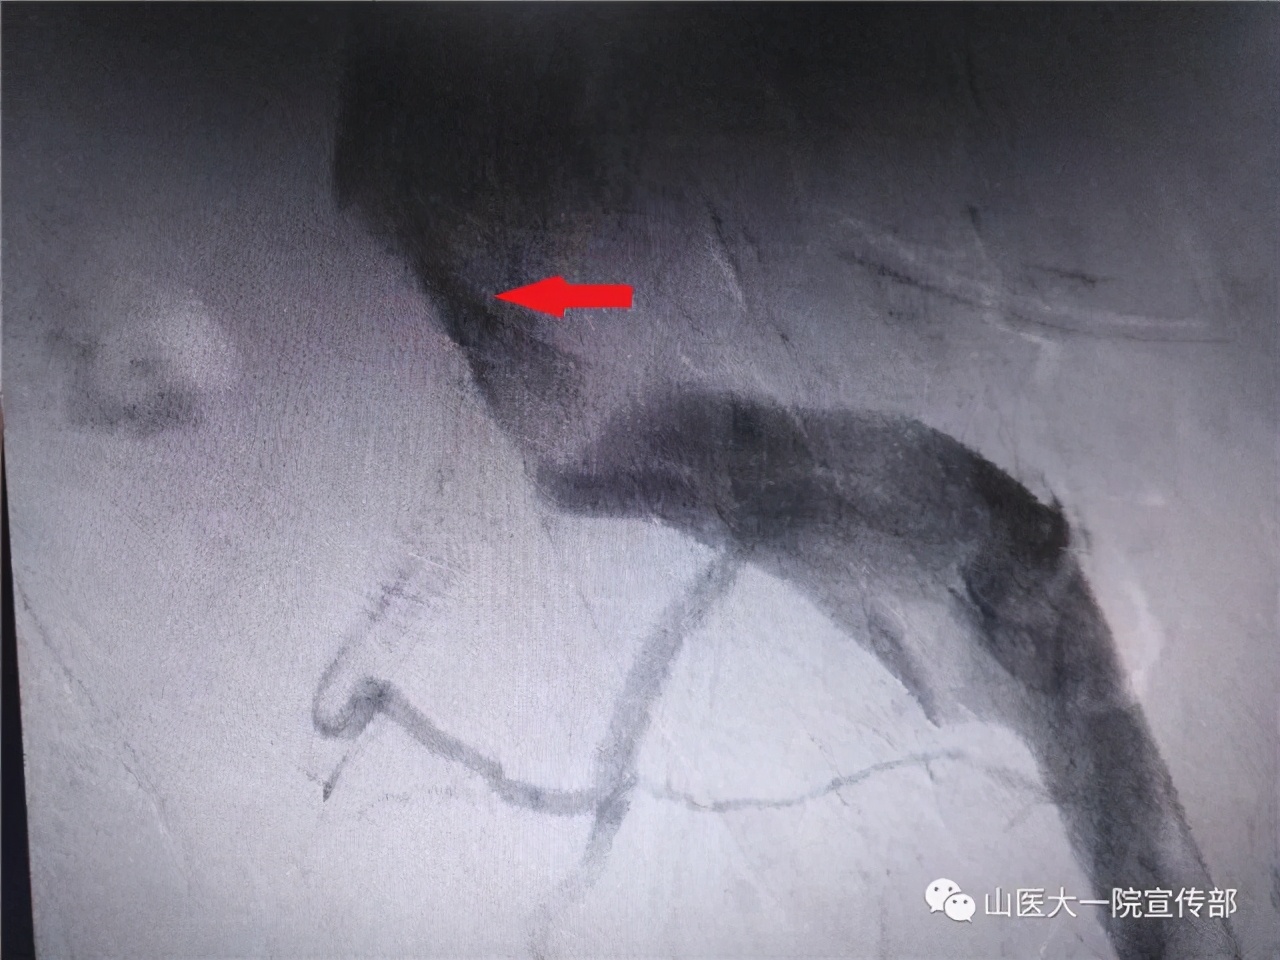

血管外科王贵明主任通过DSA造影明确了王女士的问题所在,而一枚植入左髂静脉的支架更是解决了王女士的病痛。术后第二天排尿症状好转,术后第四天顺利排便,王女士高兴地说:“多少年了没有这么顺畅过。”

对于难以缓解的妇科盆腔胀痛的妇女,可以考虑到血管外科寻求诊治。通过血管彩超、CT血管造影、数字减影血管造影(DSA)可以明确盆腔瘀血的原因,以及是否存在Cockett综合征。介入治疗,即向狭窄的静脉管腔内置入支架,以支架的支撑力使狭窄的血管重新张开,使静脉血流通畅,缓解临床症状,因为创伤小,效果好,目前已成为这一病症的首选。(责编 白金 通讯员 梁芳)